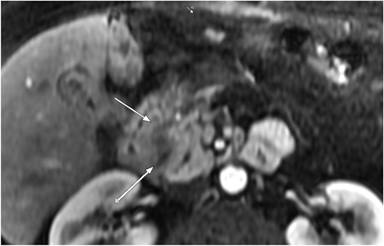

An alternative approach is to perform advanced image feature analysis. One such feature is the density of a mass on CT (Choi’s critera) rather than a single dimension, as with RECIST. Vecchiarelli et al. showed that the Choi’s criteria may be a better biomarker of overall survival than RECIST [9]. One reason for concern with monitoring changes in the imaging features of pancreatic adenocarcinoma on imaging is the ill-defined margins that are classic for this cancer (Figure 1). Therefore, differences in imaging parameters and difficulty in identifying the full volume of the mass may cause this technique to fail when applied in multiple centers.

Figure 1. Contrast enhanced MRI of pancreatic adenocarcinoma (arrows) with the characteristic ill defined margins that render this type of cancer difficult to delineate. |